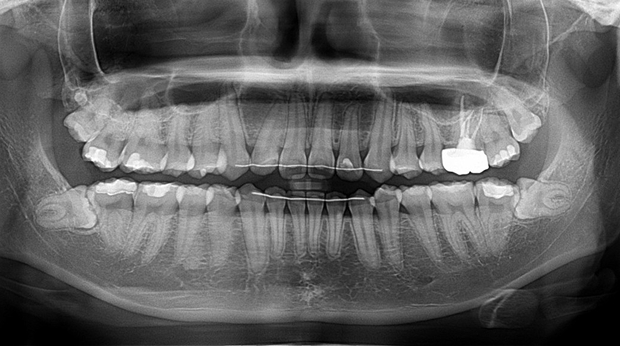

매복 사랑니 발치

의식하진정법(수면마취)/임플란트

수술 담당 구강악안면외과 전문의

고난도 수술 진료

임플란트와 사랑니 발치는 외과적 시술로 잇몸을 절개하는 외과적 시술은

짧으면 짧을 수록 시술 후 붓기와 통증이 최소화됩니다.

치과의사 경력 14년차 구강외과 전문의가 빠르고 안전하게, 아프지 않게 수술해 드립니다.